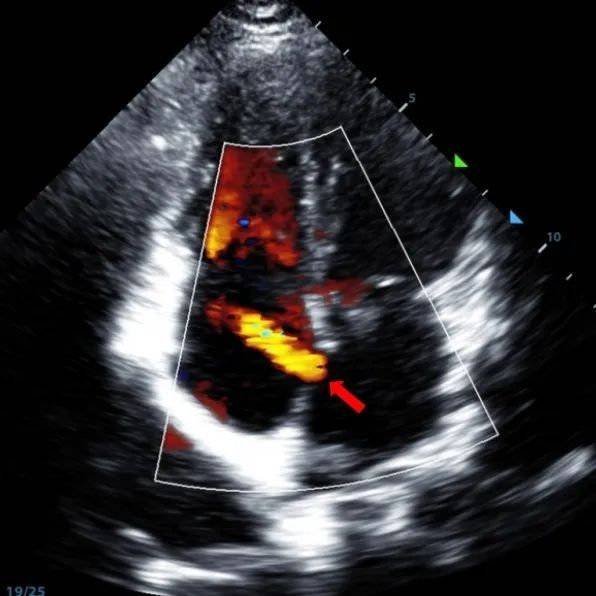

9-летний мужчина с секундовым ASD (7,5-7,9 мм) был обработан с использованием окклюдера MemoSorb BDASD-I 12 мм и системы доставки 12F. Никаких осложнений или сопутствующих заболеваний не было отмечено до процедуры.

Serial echocardiographic follow-ups showed stable device position and favorable cardiac remodeling. Gradual degradation confirmed the occluder's long-term safety and efficacy.